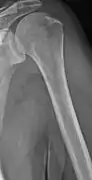

The diagnostic examination of a person with suspected multiple myeloma typically includes a skeletal survey. This is a series of X-rays of the skull, axial skeleton, and proximal long bones. Myeloma activity sometimes appears as "lytic lesions" (with local disappearance of normal bone due to resorption) or as "punched-out lesions" on the skull X-ray ("raindrop skull"). Lesions may also be sclerotic, which is seen as radiodense.[70] Overall, the radiodensity of myeloma is between −30 and 120 Hounsfield units (HU).[71] Magnetic resonance imaging is more sensitive than simple X-rays in the detection of lytic lesions, and may supersede a skeletal survey, especially when vertebral disease is suspected. Occasionally, a CT scan is performed to measure the size of soft-tissue plasmacytomas. Nuclear Medicine Bone scans are typically not of any additional value in the workup of people with myeloma (no new bone formation; lytic lesions not well visualized on nuclear bone scan).

- Humerus with multiple myeloma lesions

- Same humerus before, with just subtle lesions